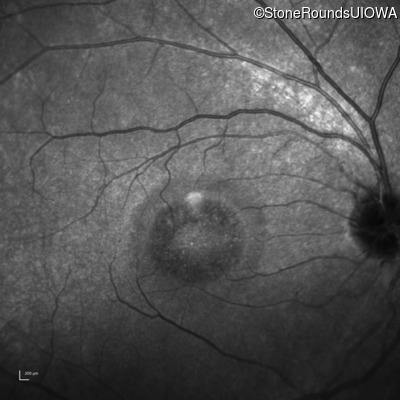

Infrared Fundus Photograph - Right - 20/40 -2 sc

Exemplar